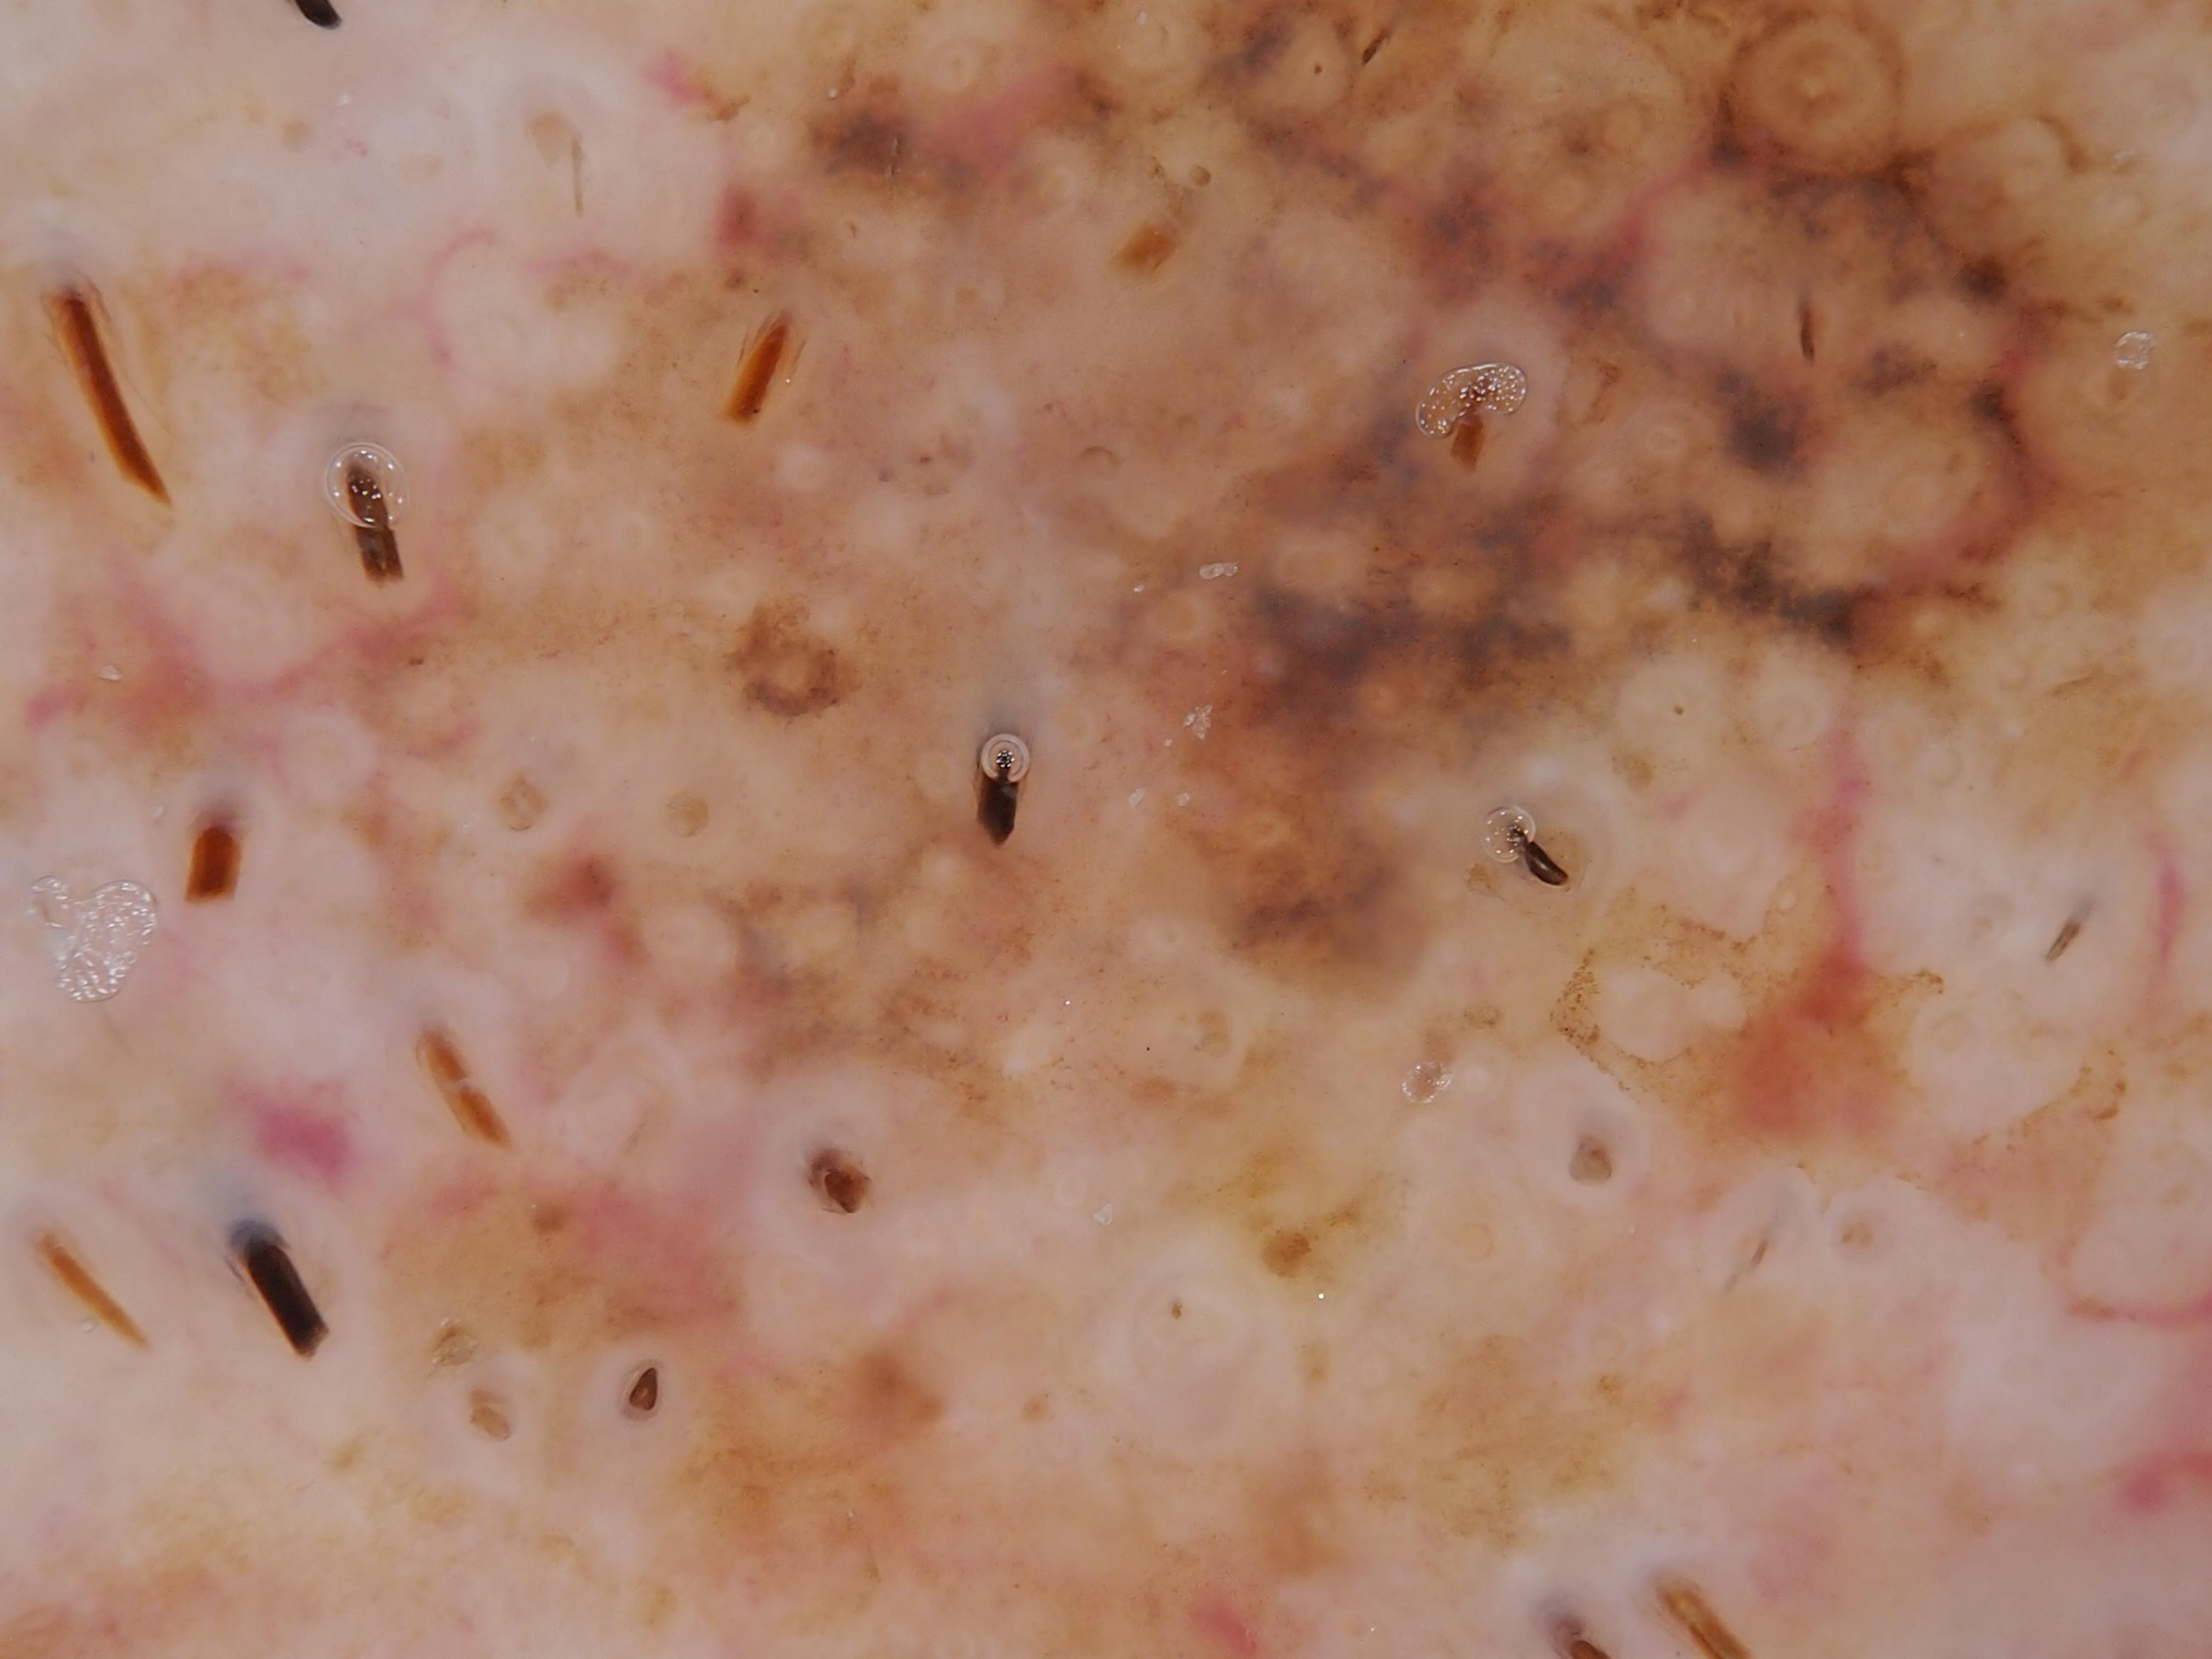

{

"age_approx": 75,

"anatom_site_general": "posterior torso",

"concomitant_biopsy": true,

"diagnosis_1": "Malignant",

"diagnosis_2": "Malignant melanocytic proliferations (Melanoma)",

"diagnosis_3": "Melanoma, NOS",

"diagnosis_confirm_type": "histopathology",

"image_type": "dermoscopic",

"lesion_id": "IL_6729488",

"melanocytic": true,

"patient_id": "IP_1422713",

"sex": "male"

}